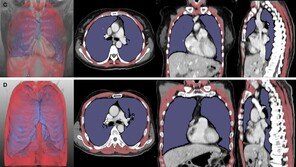

국내 연구진이 인공지능 딥러닝 기술로 흉부 컴퓨터단층촬영(CT) 영상을 분석해 루게릭병 환자의 호흡 기능을 평가할 수 있는 새 지표를 만들었다. 루게릭병 환자의 호흡 기능 평가는 주로 폐활량 검사를 통해 이뤄지지만, 구강안면 근육이 약한 환자는 검사 정확도가 떨어진다. CT 영상을 통…